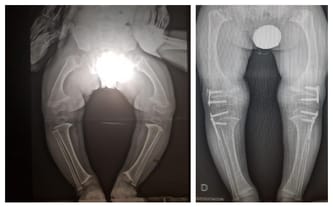

dzięki Waszemu wsparciu Jurek przeszedł poważną operację bioder, która trwała około 5 godzin. Zostały mu założone płytki, dzięki którym dr Paley mógł ustawić biodra w prawidłowej pozycji.